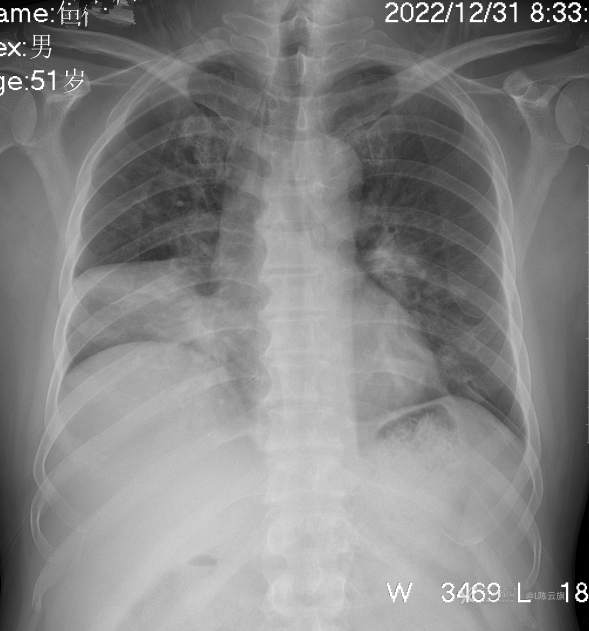

1、男51岁,精神病住院一个多月,出现持续发烧两天,伴咳嗽气紧,少痰。

2、胸片典型病例,这是什么典型呢?